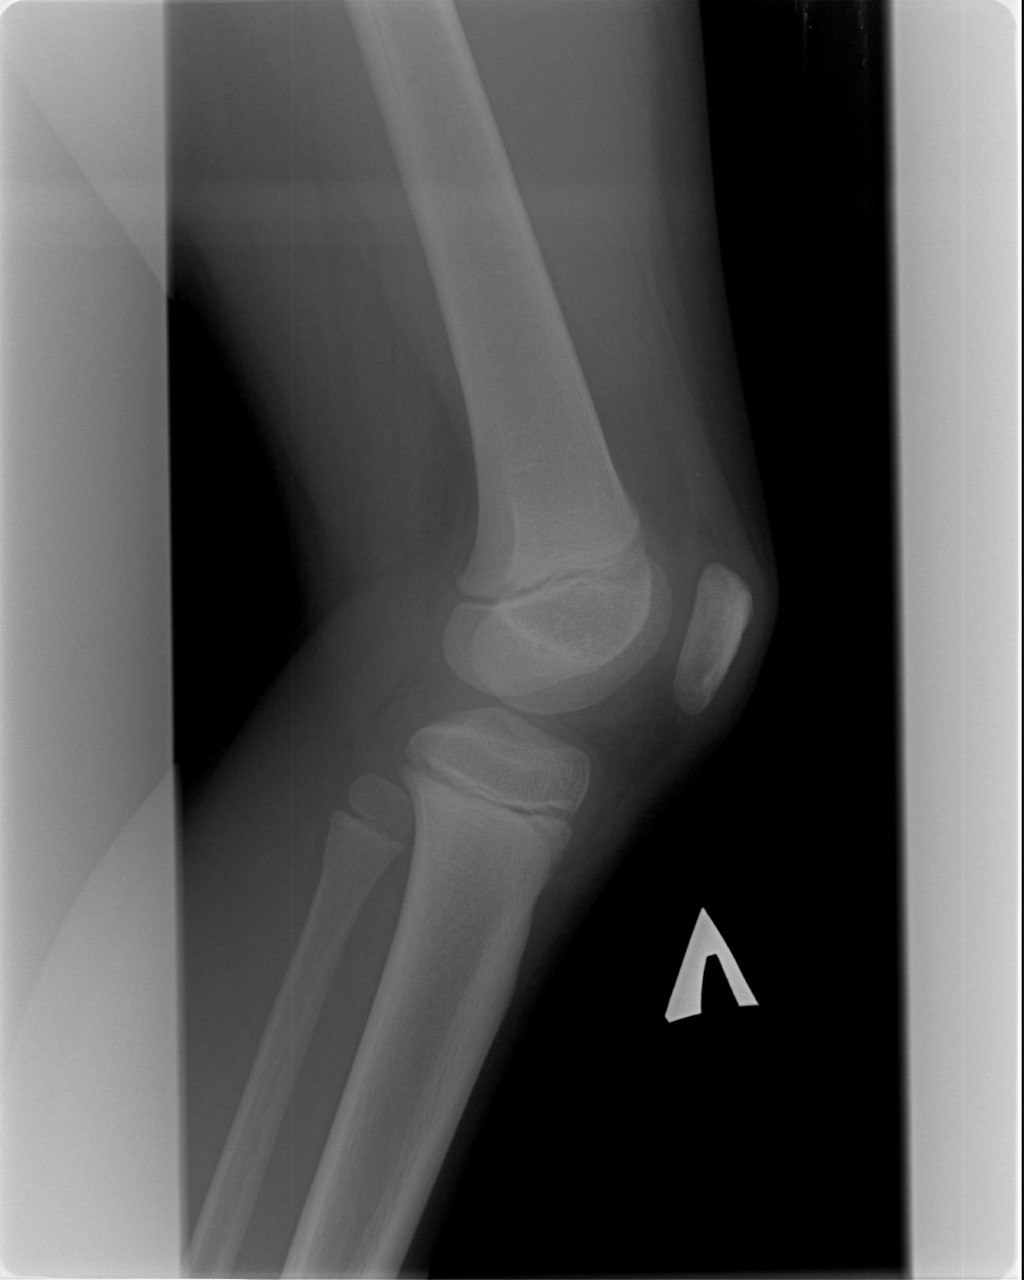

Ларсена йохансона

Ларсена йохансона 146 фото